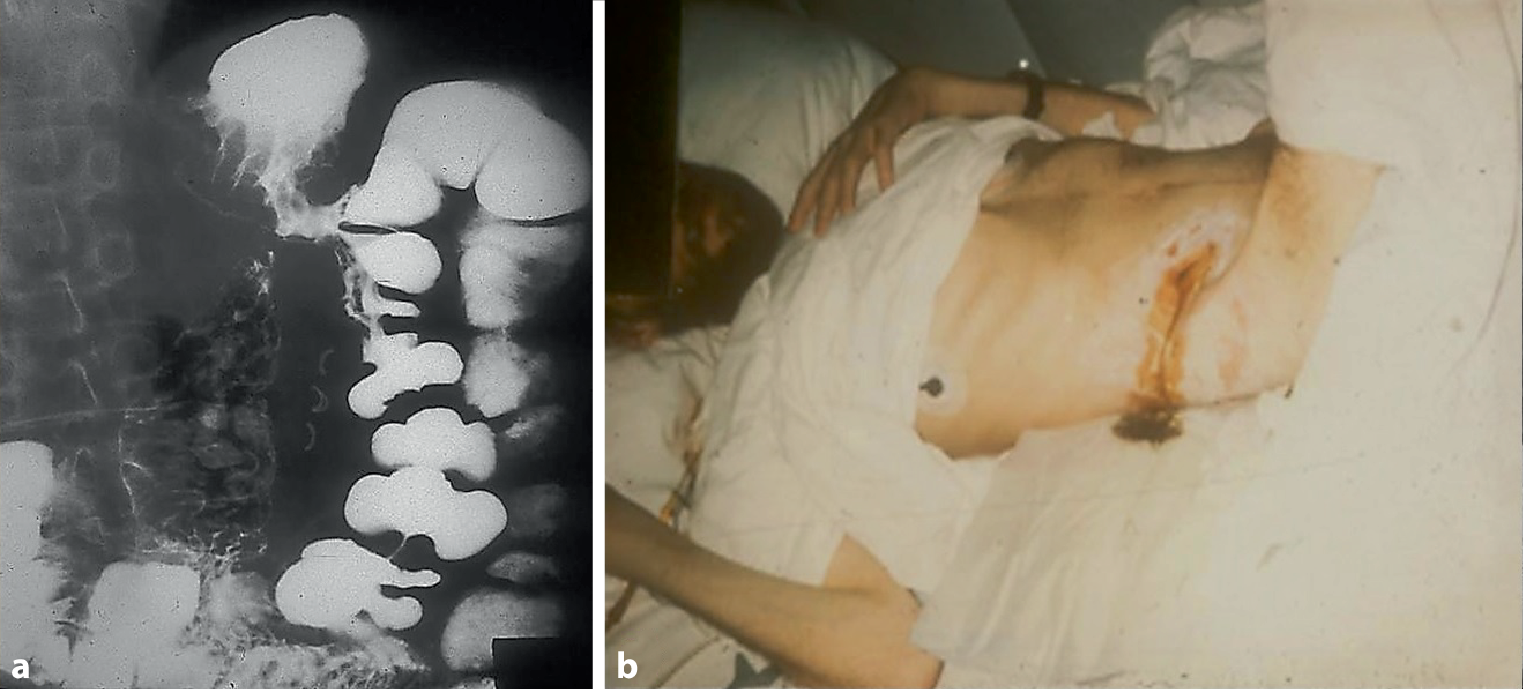

Dr. G. J. Krejs: Symptoms of gastrointestinal fistulas are variable and depend on their location. Fistulas that connect the colon to another part of the intestine may result in osmotic diarrhea because of insufficient surface for absorption. This condition tends to worsen with eating [26]. Weight loss caused by the ensuing malabsorption is frequently observed in affected patients. In former days, when proton pump inhibitors were not available and Helicobacter pylori was still unknown, gastric ulcers were rather common. Secondary to chronic ulcers, some patients developed gastrocolonic fistulas (Fig. 3), which led to a markedly reduced gastrointestinal transit and the finding of undigested food in the stool. Indeed, undigested food in stool is a hallmark of fistulas from the very proximal to the very distal gastrointestinal tract. Evaluation of the patient’s anatomy is a must in such cases.

Fig. 3

Barium swallow showing a gastrocolonic fistula (a). Patient with Crohn’s disease and an enterocutaneous fistula with stool leakage (b)

However, colonic fistulas may also connect the intestine with the skin, the bladder or vagina, and cause abnormal fluid, stool and gas passage. Before the availability of effective treatment, patients with chronic inflammatory bowel disease were prone to such complications (Fig. 3). Rarely, colobronchial fistulas are also observed; Zhao et al. [27] and our team reported such cases [28].